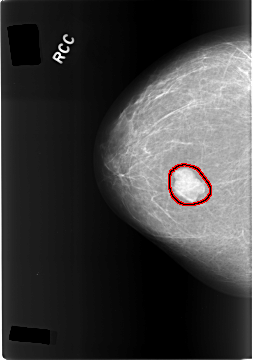

C_0305_1.RIGHT_CC

FILE: C_0305_1.RIGHT_CC.OVERLAY

TOTAL_ABNORMALITIES 1

ABNORMALITY 1

LESION_TYPE MASS SHAPE LOBULATED MARGINS CIRCUMSCRIBED

ASSESSMENT 4

SUBTLETY 5

PATHOLOGY BENIGN

TOTAL_OUTLINES 1

BOUNDARY